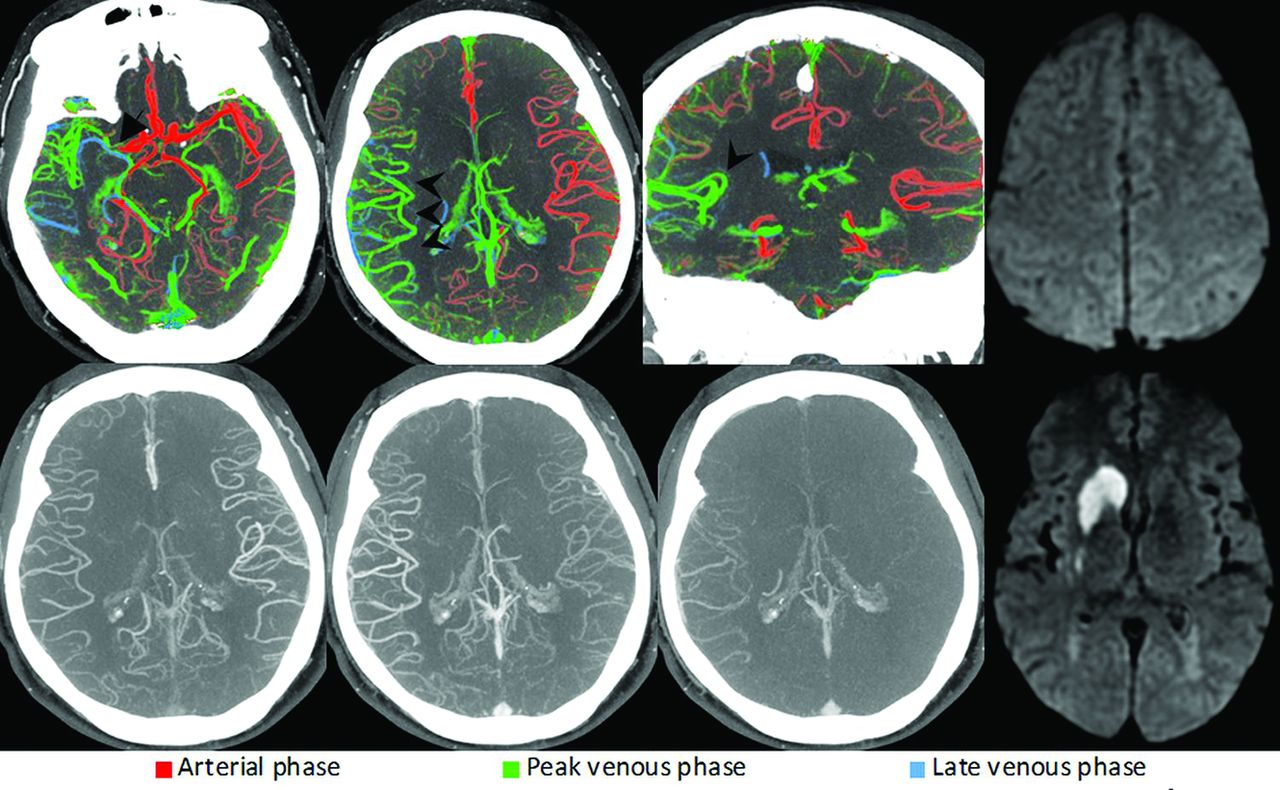

Bilateral M3 segment MCA occlusions (arrows) visualized through changes in the pial artery color compared with the surrounding pial arteries. Some cortical MCA branches of both hemispheres are depicted in green and blue (arrowheads), consistent with bilateral occlusions. Due to the symmetry of the occlusions, they are difficult to appreciate on conventional mCTA (lower row). CTP (lower right) shows prolonged time-to-maximum times in the affected territories, confirming the suspected occlusions.